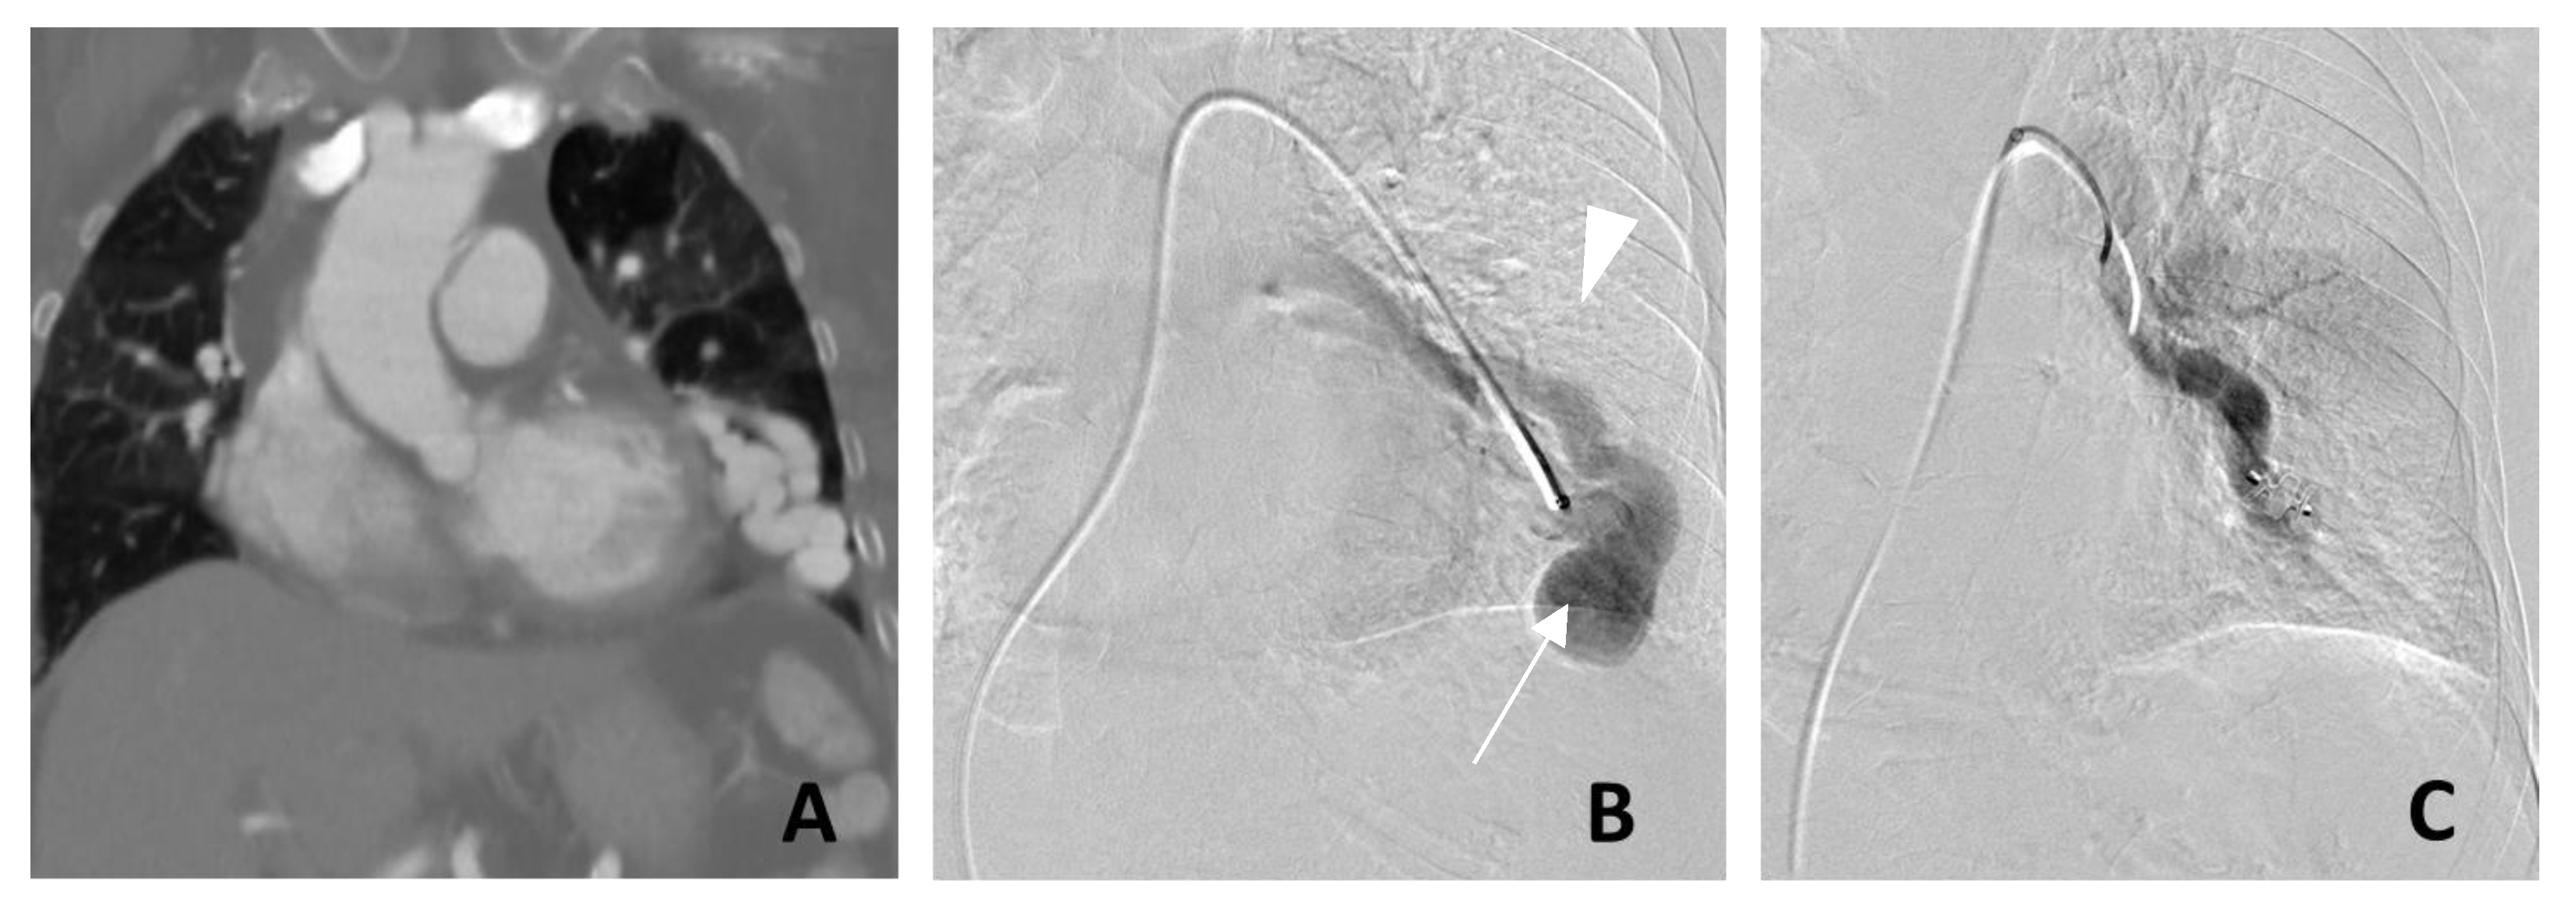

3. Management of PAVM